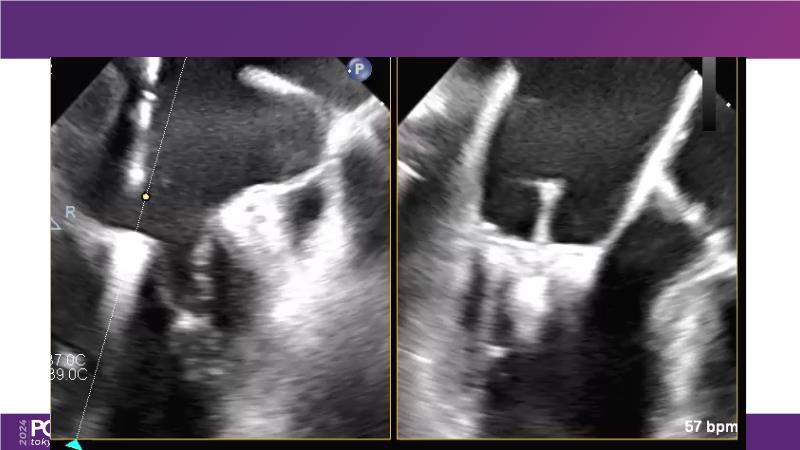

Watch this session to get an overview of a new TEER device, follow the step-by-step procedure related to initial experiences with this device for a Japanese patient with degenerative mitral regurgitation, learn about the latest data from RCT and registries, and follow discussions of challenging TEER cases!

- To understand how novel TEER device provides new possibilities in TEER

- To learn procedural step-by-step of novel device